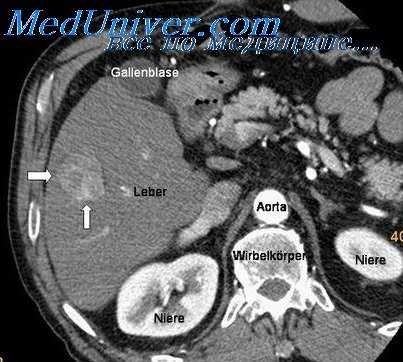

Выполнена мультиспиральная компьютерная томография (КТ) органов грудной клетки, брюшной полости и малого таза. Данных о метастатическом поражении легких не получено, выявлен диффузный пневмосклероз, признаки хронической обструктивной болезни легких (ХОБЛ), данных о наличии метастазов в печени не получено, имеются признаки жирового гепатоза печени, в проекции входа в малый таз в сигмовидной кишке определяется утолщение ее стенки до 19 мм на протяжении до 40 мм (рис. 5). В теле матки определяются обызвествленные округлые миоматозные узлы; забрюшинные лимфатические узлы и узлы малого таза не увеличены.